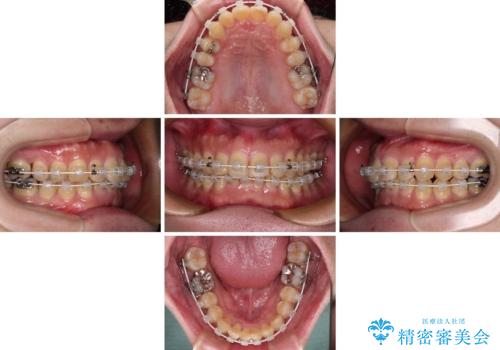

深い咬み合わせで顎が疲れる ワイヤー矯正でディープバイトを解消

- 深い咬み合わせによる食いしばりで、顎関節や頭が痛むことがあるとのことで来院された患者様です。

歯ぎしりができないくらい強い食いしばりの咬合状態であったため、奥歯の歯軸を起き上がらせることで咬合を挙上させ、歯ぎしりができるようにしていくこととしました。

インビザラインでの矯正治療も可能でしたが、自己管理の煩わしさを嫌ってワイヤー装置による矯正治療を行うこととしました。

下顎が左側にずれているため、上下正中は最大限合わせられるところまで合わせるゴールとなりました。